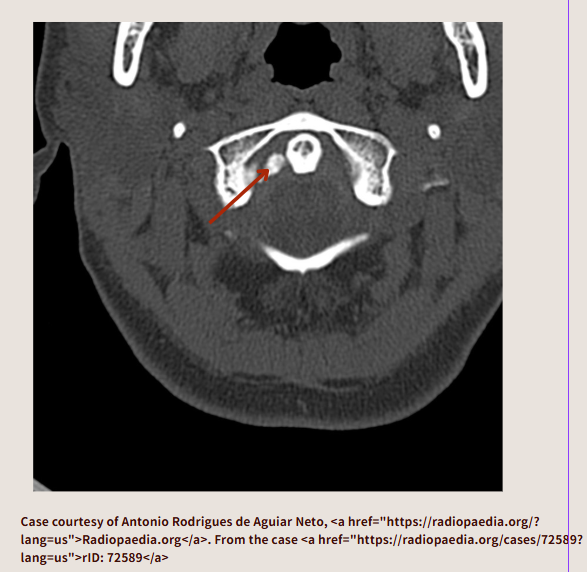

下のCT画像では、歯尖靭帯に石灰化が見られます。(赤矢印は自分で追加)